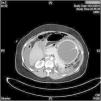

A 53-year-old woman came to the emergency room reporting diffuse abdominal pain and vomiting in the previous 16 h. She reported insertion of an Orbera® intragastric balloon (IGB) 4 months earlier, with no incidents. Computed axial tomography revealed a rupture in the gastric fundus, with pneumoperitoneum and abundant food content observed in the abdominal cavity (Fig. 1).